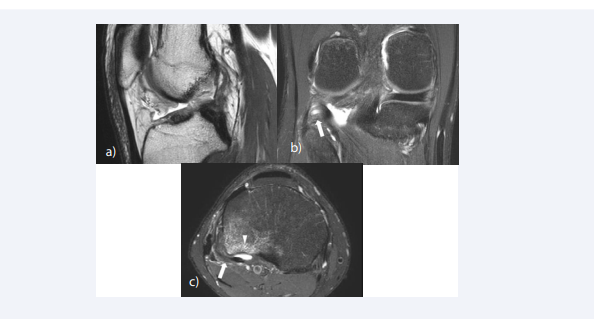

Meniscal tears are frequently associated with ACL tears; the reported frequency is 39.6-73.0% [82-87]. Lateral meniscal tears are more commonly seen in acute ACL tear, whereas medial meniscal tears are more frequent in chronic injuries [88]. Meniscal tears are commonly located at the posterior horn, comprising 95% of the medial meniscal tears and 77% of the lateral meniscal tears [89]. Vertical longitudinal tear is the most common type of meniscus tear for both medial and lateral menisci in patients with ACL injuries [90-92] (Figure 7). Previous studies have reported that performing meniscus repair along with ACL reconstruction, may help restore knee kinematics, and improve patient-reported outcome [93-95].

Associated injury of the meniscus. (A) Sagittal fat-suppressed – weighted image shows discontinuity of the ligament fibers with sagging of the ligament, and  increased signal intensity. (B) A vertical longitudinal tear is noted in the posterior horn of the medial meniscus

FIgure 7: Associated injury of the meniscus. (A) Sagittal fat-suppressed – weighted image shows discontinuity of the ligament fibers with sagging of the ligament, and increased signal intensity. (B) A vertical longitudinal tear is noted in the posterior horn of the medial meniscus

The clinical significance of meniscal ramp lesions in patients with ACL tear has gathered attention in the past decade. Meniscal ramp lesions refer to the tear, disruption, or separation of meniscocapsular junction of the posterior horn of the medial meniscus, which usually occur after traumatic knee injuries. Undiagnosed ramp lesions may lead to knee instability (anterior translation and external rotational laxity), aggravation of medial meniscus posterior horn tear and accelerated degeneration of both the meniscus and the articular cartilage [96]. Therefore, it is important to recognize ramp lesions in patients sustaining ACL injury. On MRI, ramp lesions are noted as a thin fluid signal interposed between the posterior horn of the medial meniscus and the posteromedial capsule (Figure 2d).

Anterolateral ligament (ALL) injuries are found with varying severity and intensity in patients with acute ACL tear. ALL abnormalities have been reported to occur in 46 to 78.8% of ACL injuries in studies based on MR imaging [104,105] (Figure 9). The ALL functions as a stabilizer that resists anterior tibial translation, internal tibial rotation and pivot shifting, secondary to the ACL [106]. Failure to identify ALL injury may result in persistent instability following ACL reconstruction [107]. Concurrent reconstruction of the ACL and ALL significantly reduces internal rotation and axial plane tibial translation compared with isolated ACLR in the presence of ALL deficiency [108].

Associated injury of the anterolateral ligament (ALL) and medial meniscus (A) Oblique sagittal T2-weighted image shows a complete tear of the ACL at  the mid-substance. The proximal stump appears vertical to the Blumensaat line, whereas the distal stump appears horizontal. (B) On coronal fat-suppressed proton  density-weighted image, the ALL shows increased signal intensity near the tibial attachment (arrow) and periligamentous edema, indicating injury of the ligament.  Bone contusion is also noted at the lateral femoral condyle (arrowhead). (C) Axial fat-suppressed proton density-weighted image shows increased signal intensity of  the anterolateral ligament (arrow) and bone contusion at the posterior aspect of the lateral tibial plateau (arrowhead). (D) A vertical longitudinal tear is noted at the  posterior horn of the medial meniscus.

FIgure 9: Associated injury of the anterolateral ligament (ALL) and medial meniscus (A) Oblique sagittal T2-weighted image shows a complete tear of the ACL at the mid-substance. The proximal stump appears vertical to the Blumensaat line, whereas the distal stump appears horizontal. (B) On coronal fat-suppressed proton density-weighted image, the ALL shows increased signal intensity near the tibial attachment (arrow) and periligamentous edema, indicating injury of the ligament. Bone contusion is also noted at the lateral femoral condyle (arrowhead). (C) Axial fat-suppressed proton density-weighted image shows increased signal intensity of the anterolateral ligament (arrow) and bone contusion at the posterior aspect of the lateral tibial plateau (arrowhead). (D) A vertical longitudinal tear is noted at the posterior horn of the medial meniscus.